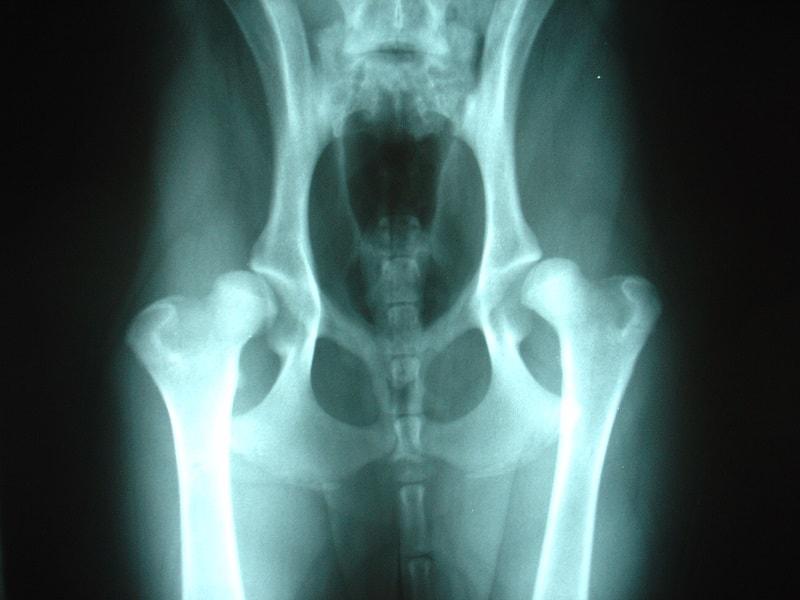

Displasia de cadera

Típica de perros grandes como mastín o pastor alemán y es hereditaria. La displasia de cadera puede presentarse en jóvenes, por lo que es aconsejable realizar radiografías para un diagnóstico precoz, en los perros viejos también es frecuente.

El acetábulo hueco es el hueco en la pelvis que aloja la cabeza del fémur. En la displasia, este hueco y la cabeza del fémur se van deformando hasta que la cabeza entra y sale del acetábulo. Esto produce dolor y cojera, los perros no desean saltar y toleran menos el ejercicio o les cuesta levantarse y subir escaleras. Su marcha suelen ser balanceante, cambian el peso evitando apoyar la extremidad que les duele.